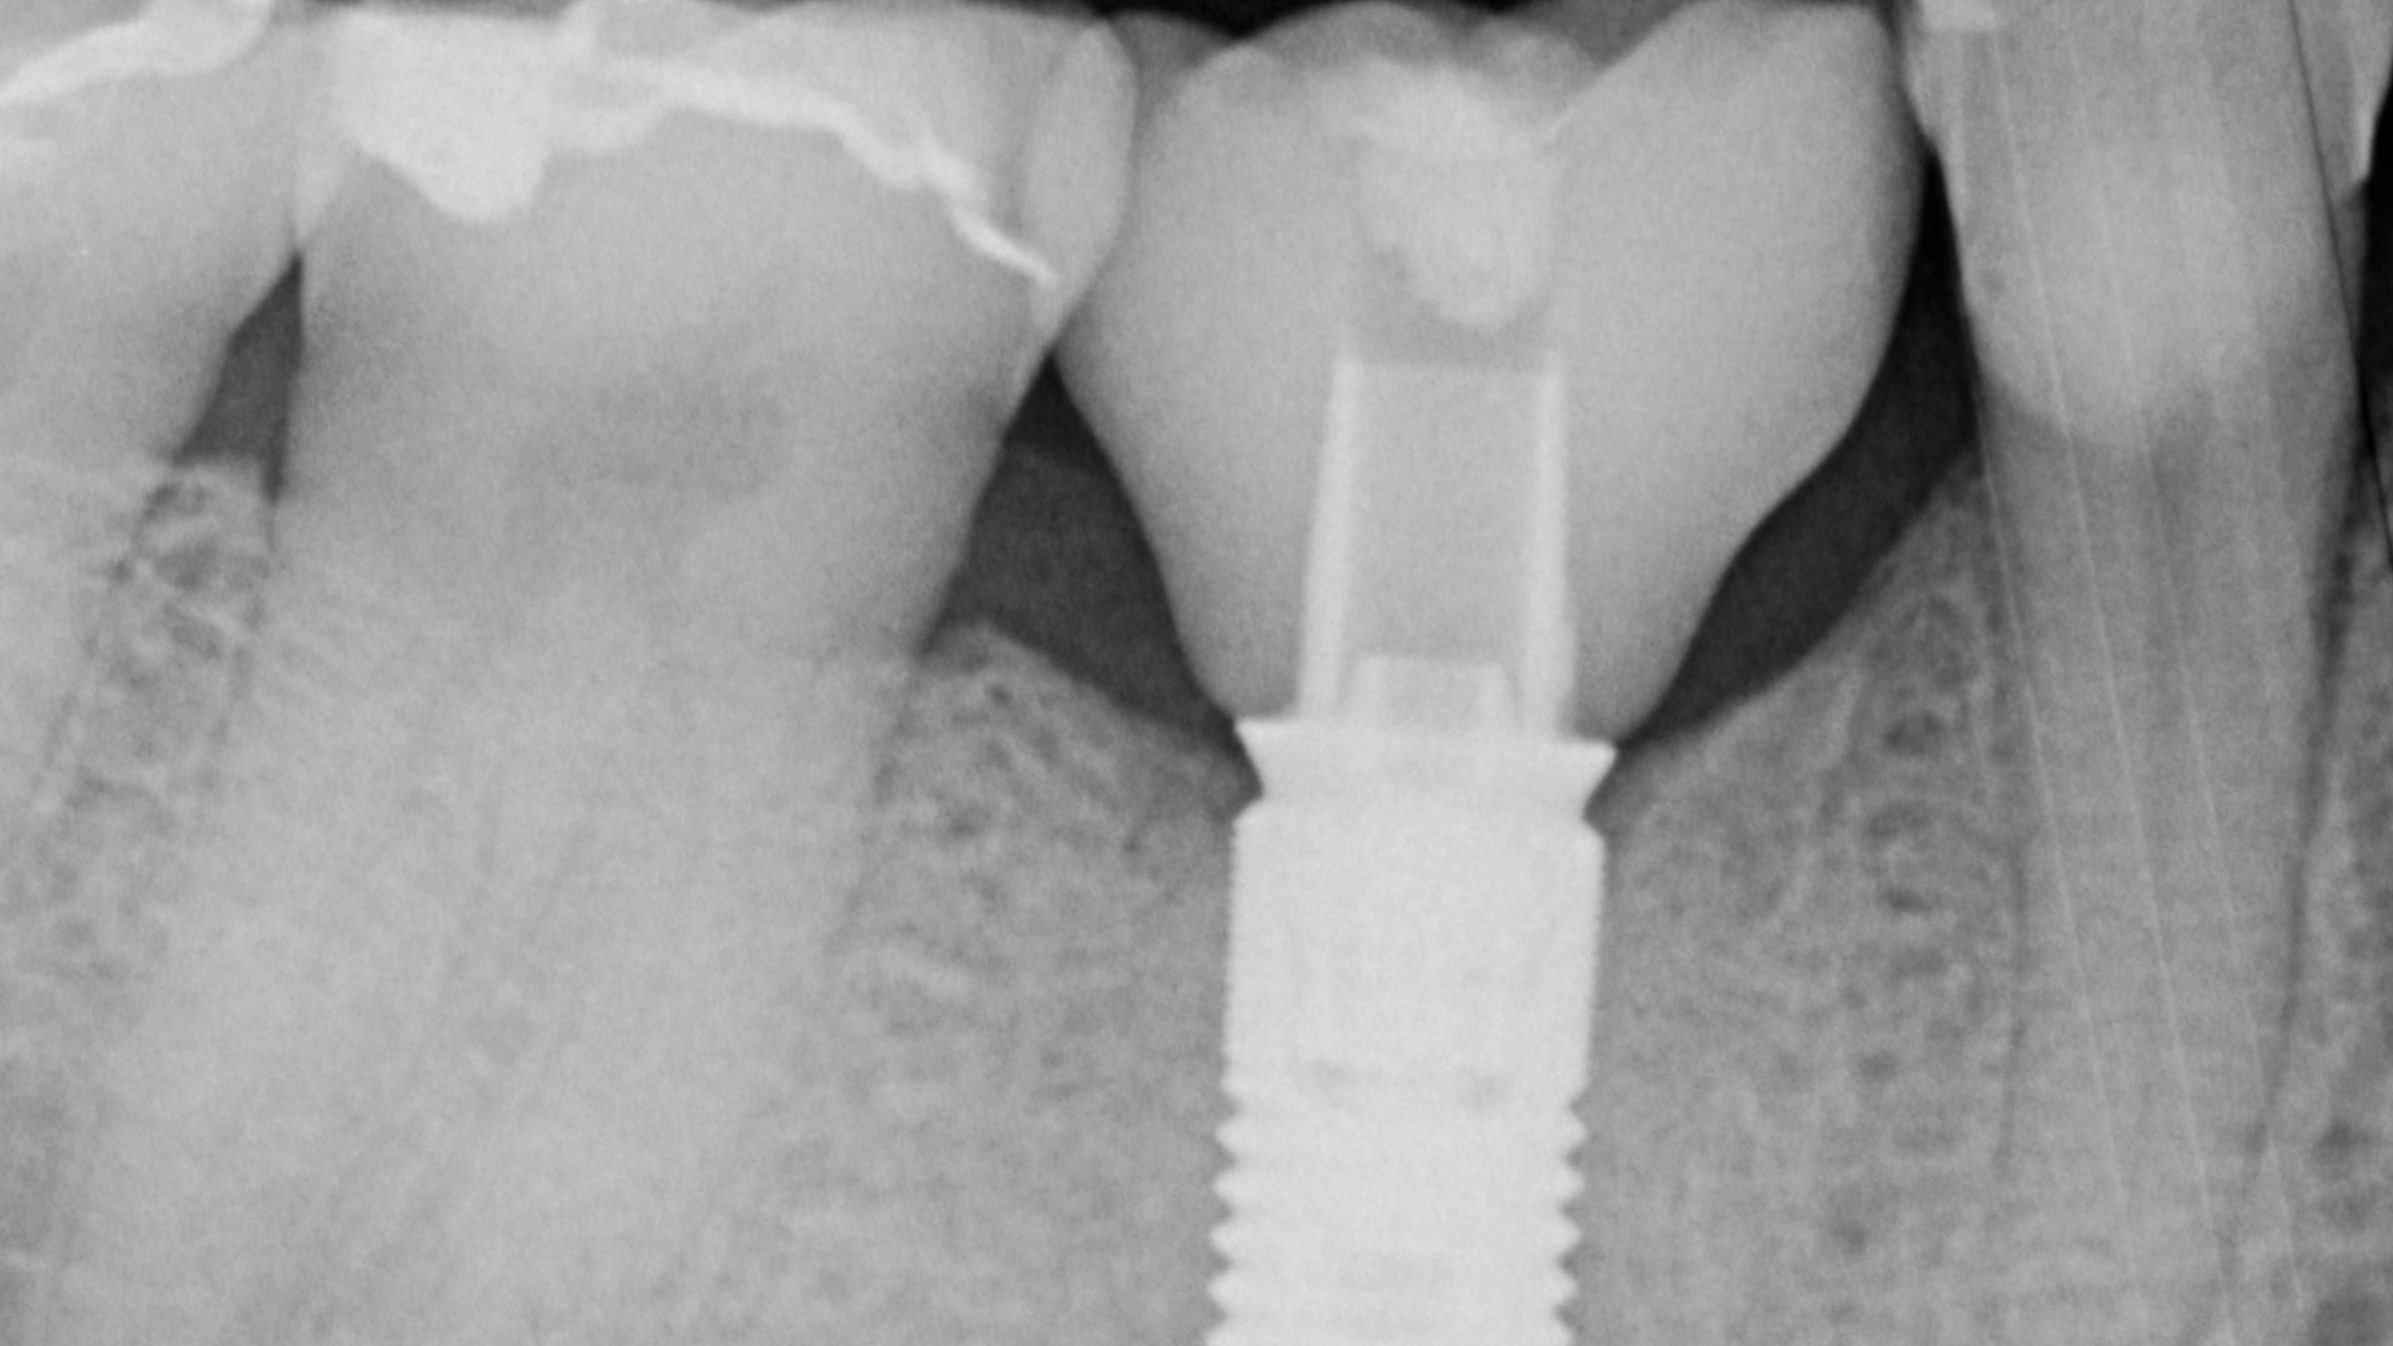

- Scannen von Implantaten mit intraoralem Scanpost und Scanbody

Implantatversorgungen mit CEREC: Abutmentkronen (e.maxCAD meso), individuelle Abutments (Zirkonoxid & e.maxCAD); Schnellsinterung von Zirkonoxid, Implantatkronen, Verkleben der Implantatversorgungen mit den Titanbasen. Besprechung von komplexen Sonderfällen an mitgebrachten Modellen ist möglich. Jeweils 2 Kursteilnehmenden steht ein CEREC-Gerät zur Verfügung.